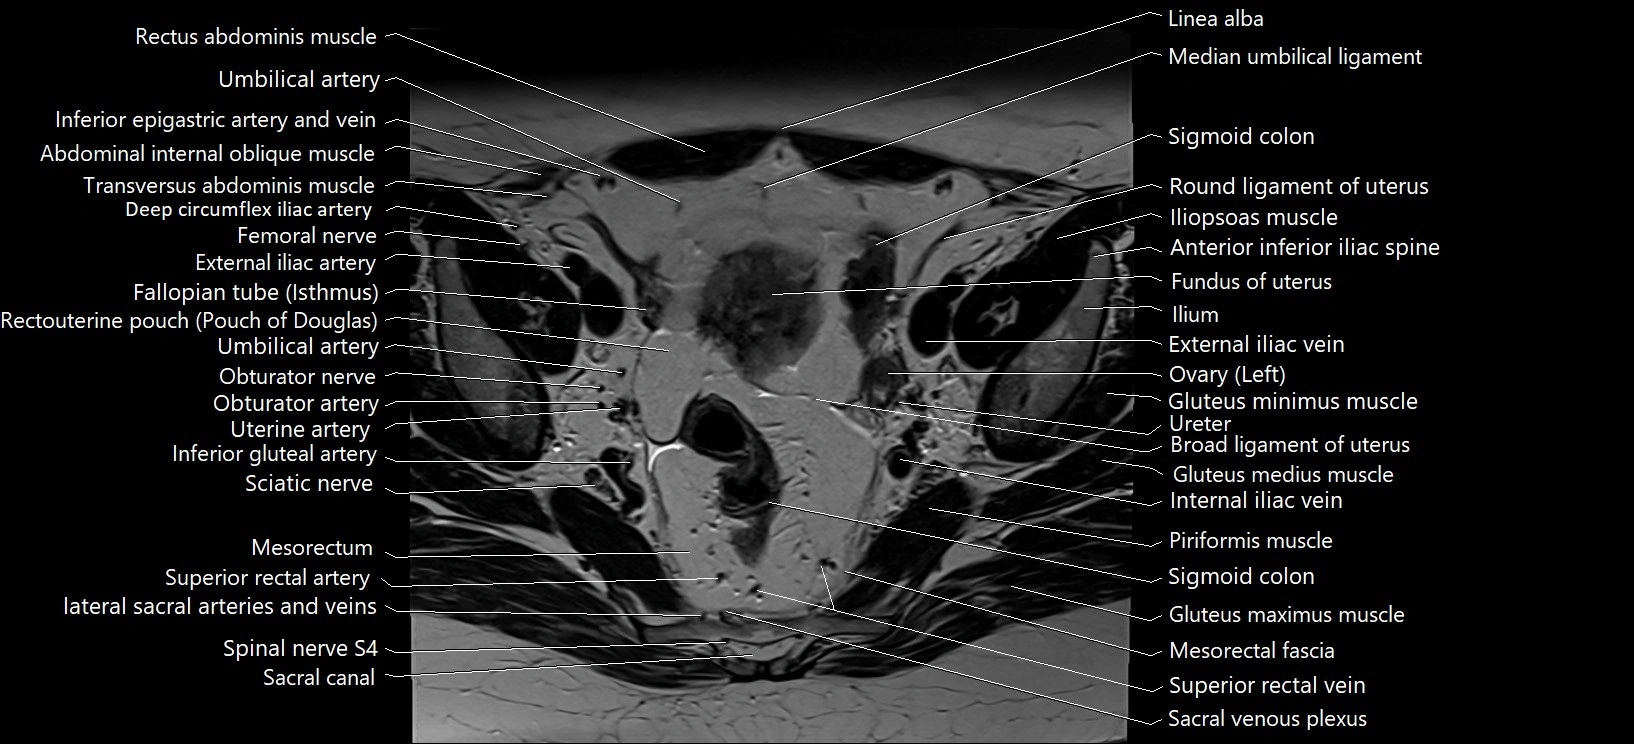

- Broad ligament of uterus

- Common iliac lymph nodes

- Deep circumflex iliac artery

- External iliac artery

- External iliac vein

- Femoral nerve

- Fundus of uterus

- Iliococcygeus muscle

- Inferior mesenteric artery (IMA)

- Internal iliac vein

- Left ovary

- Marginal artery of Drummond

- Median umbilical ligament

- Mesorectal fascia

- Mesorectum

- Piriformis muscle

- Round ligament of uterus

- Sacral canal

- Sigmoid colon

- Spinal nerve S4

- Superior rectal artery

- Superior rectal vein